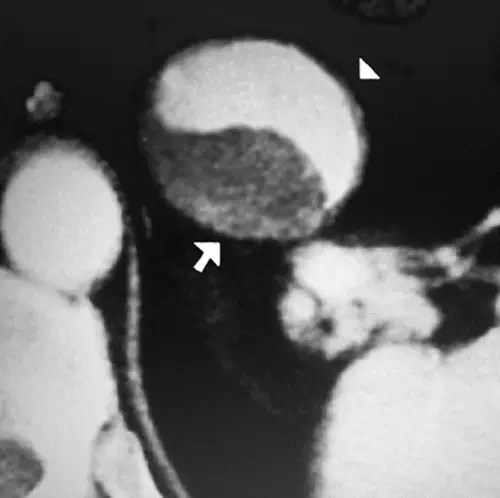

阴阳征表现为增强CT上,在扩张的卵圆形动脉截面内,可见半强化和半无强化区,形态酷似道教的阴阳符号。

阴阳征见于附壁血栓形成的真性和假性动脉瘤患者。动脉瘤为局限性或弥漫性的动脉管腔扩张,大于其正常直径的50%。假性动脉瘤指动脉管壁被撕裂或穿破,血液自此破口流出而被主动脉邻近的组织包裹而形成血肿,多由创伤所致。大动脉瘤和假性动脉瘤容易形成附壁血栓,因此血流仅充盈部分管腔。阴阳征中,造影剂充盈增强的部分代表通畅的管腔,而无造影剂充盈的部分则代表附壁血栓的形成。

病例2:脾动脉动脉瘤患者